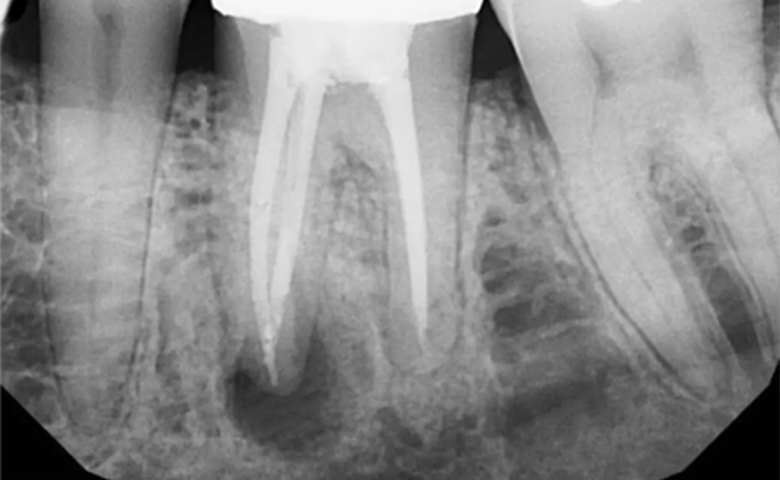

- Фіброзна стадія. Це початкова форма, для якої характерні рідкісний та незначний біль або дискомфорт. На рентгені видно незначне розширення періодонтальної щілини. Тканини навколо кореня поступово заміщуються щільною фіброзною (рубцевою) тканиною.

- Гранулююча стадія. Найбільш активна форма. Вона характеризується постійним болями, набряком ясен, часто з’являється свищ із гнійними виділеннями. На рентгені чітко видно ділянку руйнування (розрідження) кісткової тканини неправильної форми без чітких меж.

- Гранулематозна стадія. На цій стадії організм намагається ізолювати інфекційний вогнище, формуючи навколо верхівки кореня щільну капсулу — гранульому або кісту, заповнену гноєм. Біль може бути менш вираженим, але це не означає одужання. Кістка продовжує руйнуватися, утворюючи велику порожнину, що серйозно загрожує цілісності зуба.

- Постійне пломбування каналів. Після закінчення курсу ліків (зазвичай через 1-2 тижні) та отримання позитивного контрольного знімка, що підтверджує зникнення запального вогнища, проводиться остаточне щільне пломбування каналів гутаперчею.